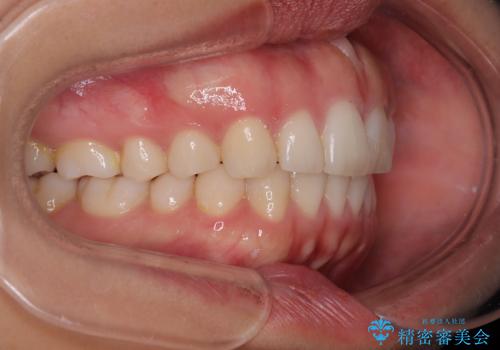

【モニター】突出した前歯 補助装置を併用したインビザライン矯正

- 上下前歯が非接触となり、前方に突出していることを気にして来院された患者様です。

咬合力が強く、全体的に歯がすり減っているため、インビザライン単独での上顎歯列移動は困難と判断し、補助装置により上顎歯列を後方移動させ、その後インビザラインにて仕上げていくこととしました。

補助装置なしでも改善できる可能性はありましたが、補助装置で確実性を上げ、短期間できっちりと仕上げることができました。